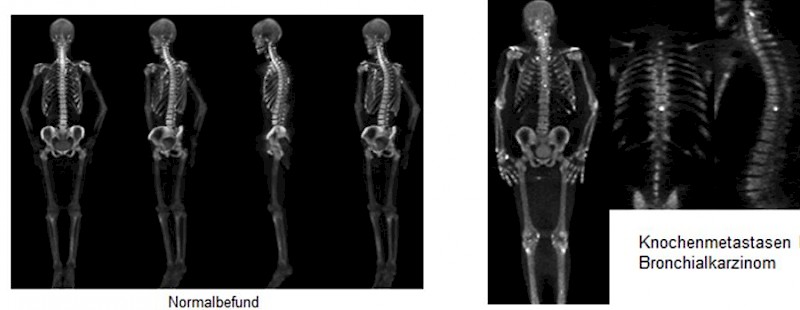

- Knochenszintigraphie mit - Natriumfluorid: Eine PET-CT-Untersuchung mit - Natriumfluorid kann den Knochenstoffwechsel besser darstellen als eine konventionelle Knochenszintigraphie (dreidimensionale Bilder des gesamten Körpers bei kurzer Aufnahmezeit, höhere Auflösung, besserer Kontrast, gleiche Strahlenbelastung).